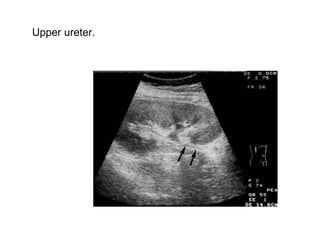

Upper ureter.